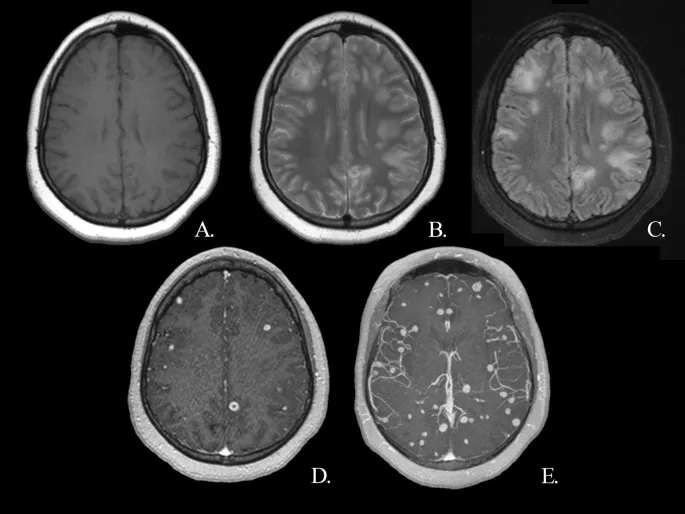

⭐ Neurocysticercosis is the most common parasitic infection of the CNS and a major cause of acquired epilepsy in developing countries.

- Neurocysticercosis (Taenia solium) is a leading cause of adult-onset seizures in endemic areas.